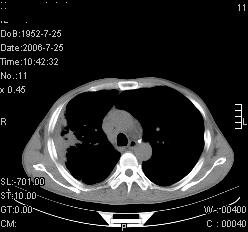

患者,男,54岁,咳嗦,咳痰20天。抗炎治疗2周。现esr76mm/h,目前患者症状明显好转,但发现两次ct片未见明显变化。两次分别做与7.25、7.31。第一次诊断右肺上叶炎症累计胸膜。大家看,从影像上内排除结核吗?

结核的可能性非常大,右上肺病变应该考虑干酪性肺炎。理由:

1.纵隔内多发淋巴结肿大。

2.esr76mm/h。

3.虽经抗炎治疗肺窗病灶有所吸收、减小,但纵隔窗病灶形态、密度、范围无明显变化。如果是单纯的大叶性肺炎,“抗炎治疗2周,目前患者症状明显好转”病灶应该基本消散了,至少也处于吸收消散期,密度变淡、范围变小。同时本病例所示其内的密度不均匀,见多发大小不一空洞样影也不符合大叶性肺炎吸收消散期表现。

病灶特点:片状 索条 结节混杂影,部分融合,密度不均,广泛累及相应胸膜.

临床治疗;二周未吸收.但症状好转.

多考虑:肺结核.